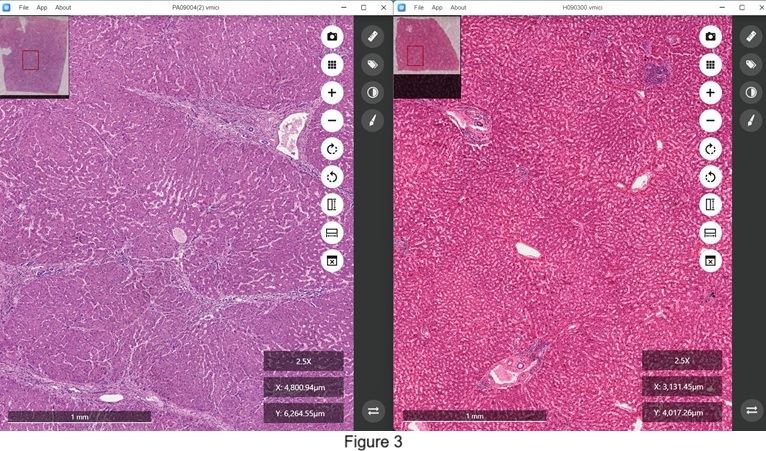

Moreover, this tool is invaluable for distinguishing between normal and diseased tissues, as shown in Figure 3. The right window displays a tissue section from a normal human liver, while the left window presents a section from a human liver affected by cirrhosis, with both sections stained using hematoxylin-eosin.